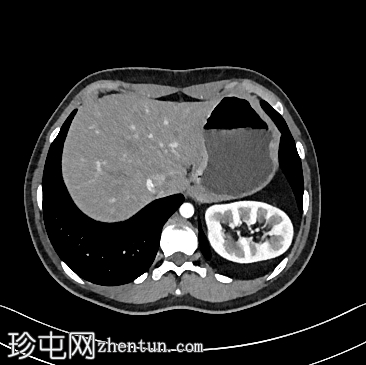

轴位增强扫描

门静脉期

左侧Bochdalek疝,大小为8.7 x 7.5 cm,疝颈长3.2 cm。左肾位于胸腔内(Bochdalek疝伴胸内肾),无并发症。左肾旋转不良(过度旋转),肾门朝向后方,肾血管位于后方。肾血管起源正常。肾脏大小为8.6 x 5.8 x 6.1 cm,体积、实质和功能均正常。输尿管膀胱连接处位置正常。未见结石或肾积水。

右肾位置正常,大小正常(头尾径 9.5 cm),肾实质和功能均正常。未见结石或肾积水。